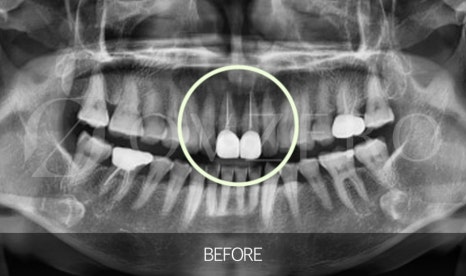

Why is root canal treatment needed?

Inside a tooth,

there is a space containing nerves and blood vessels

that sense pain.

If a cavity gets deeper,

a tooth cracks,

or strong force is repeatedly applied,

inflammation can spread to this nerve as well.

In this condition,

removing only the visible cavity is not enough,

and treatment is needed to remove the inflamed nerve

and thoroughly clean the inside of the tooth.

This is what we commonly call root canal treatment.